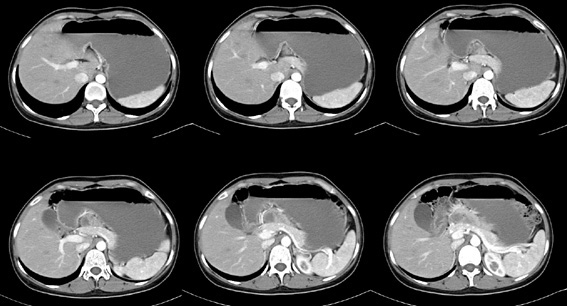

女性,28岁,停经3月,腹部膨隆1月,产前检查发现腹部占位

{肿块中心ct值27hu,增强后,动脉期、门脉期均无明显强化)

患者手术病理:腹腔囊性淋巴管瘤,象这样充满整个腹腔的的确很少见